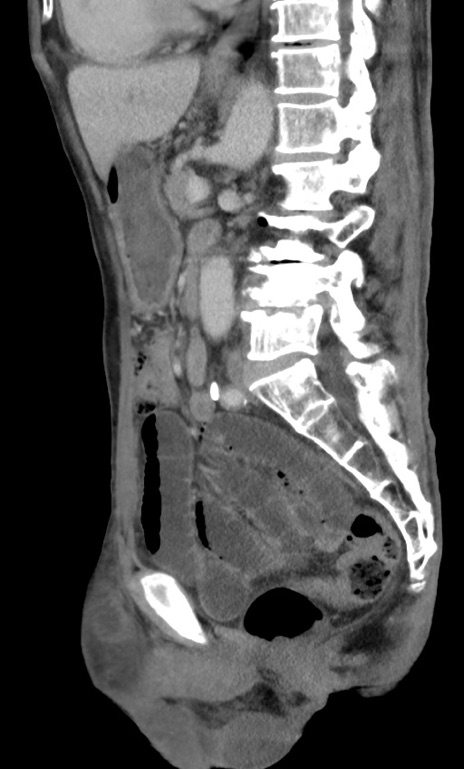

症例3(矢状断像)

【症例】 70歳代男性

【主訴】右鼠径部腫瘤、疼痛

【現病歴】本日朝より上記主訴あり、受診。

【既往歴】膀胱癌にて膀胱全摘、両側尿管皮膚瘻

【データ】WBC 5600、CRP 0.56

横断像